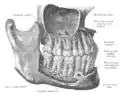

Estruturas

Fazem parte da mandíbula:

- Alvéolo dentário.

- Ângulo da mandíbula.

- Canal da mandíbula.

- Canal de Serres.

- Côndilo.

- Corpo da mandíbula.

- Forame da mandíbula.

- Forame mentual.

- Fóvea pterigóidea.

- Incisura da mandíbula.

- Língula da mandíbula.

- Linha milo-hióidea.

- Linha oblíqua.

- Processo coronóide.

- Protuberância mentual.

- Ramo da mandíbula.

- Sínfise da mandíbula.

- Sulco milo-hióideo.

- Trígono retromolar.

- Tubérculo geniano.

- Tuberosidade massetérica.

- Tuberosidade pterigóide.